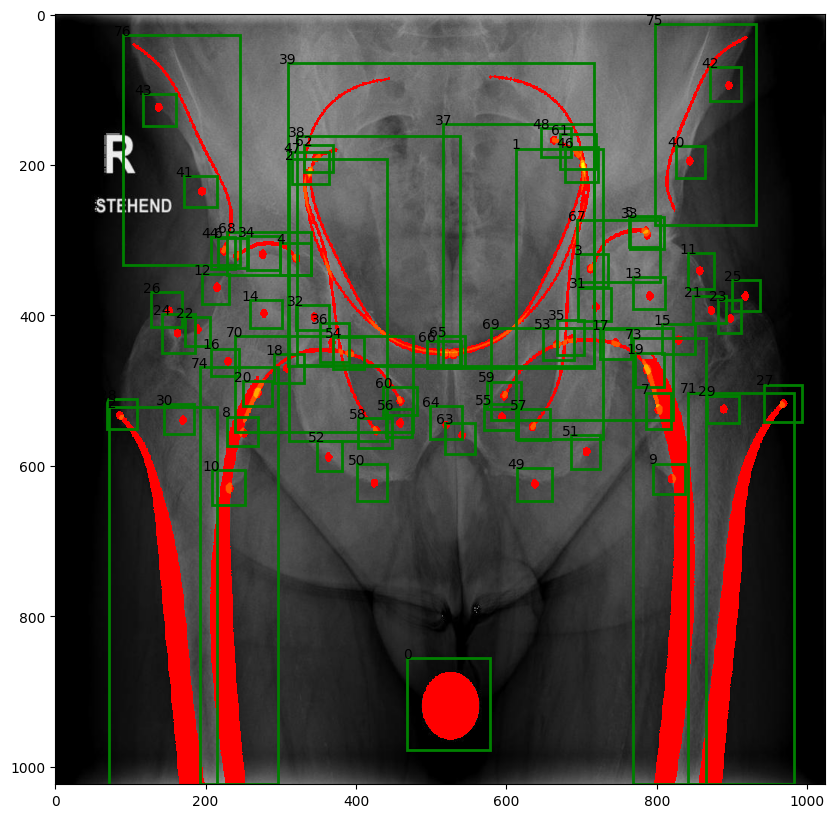

For the scaled problem, the landmarks were defined as circles of 2 mm radius. An outline is an orthopaedic line, created by the superimposition of 3D features on a radiograph. Patches fill in cortical bone of the left and right femora and the calibration ball in the middle. Some of the features overlap in part (Fig. 7).

Refer to caption

Figure 7: Ground truth data, bounding boxes, landmarks, outlines and patches.

3.5 YOLO detection

YOLO11-n model was used again in the scaled task. As in the case with eight landmarks, training was carried out for 300 epochs with sample augmentation by variation of brightness, contrast, translation, scaling and angle variation without reflection. Time of training was 30 min. The mean accuracy of landmark determination was lower in the expanded dataset (Tab. 1). Five out of 72 landmarks, i.e. 7%, were not identified. Most of these points are closely positioned on the radiograph and, hence, may be difficult to differentiate. The mean accuracy of patches, on the other hand, was high despite two out of 18 outlines, i.e. 11%, not located at all.